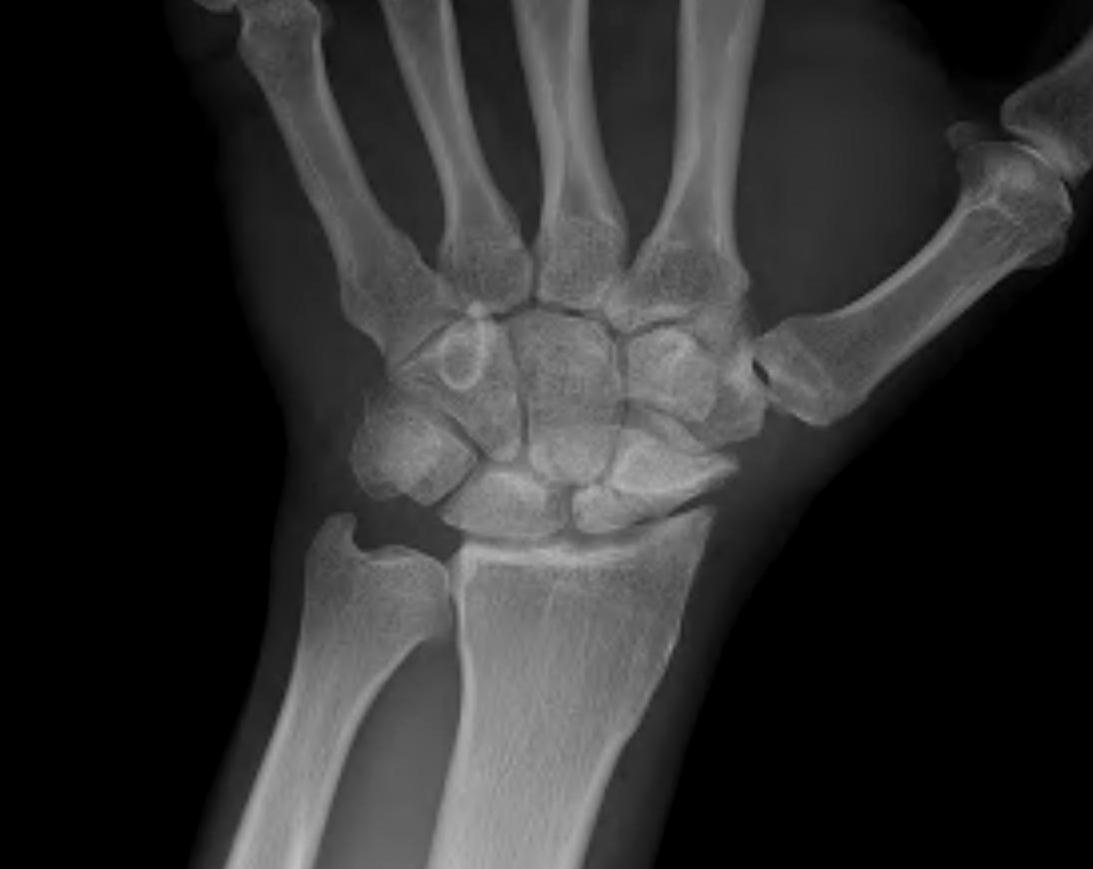

Definition

Scaphoid non union advanced collapse

Diagnosis

Xray / CT

- non union of scaphoid

- radio-scaphoid OA